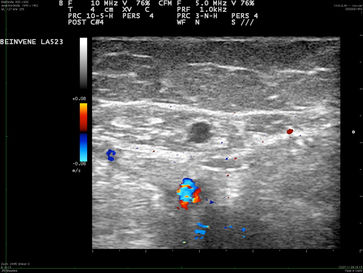

Platzierung des Radiofrequenzkatheters 1 cm vor Einmündung der Vena saphena magna in die Vena femoralis. Der Durchmesser der Vsm beträgt 7 mm.

Nach Energieapplikation ist der Durchmesser der Vsm auf 2 mm geschrumpft, das Lumen verschlossen.